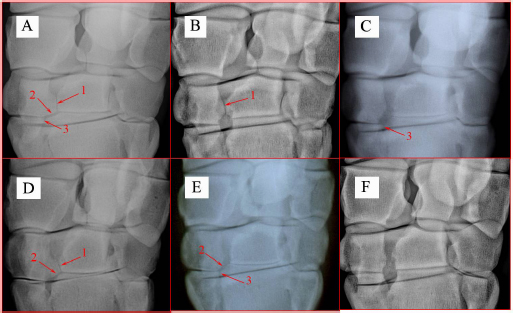

The three articulations, C2-C3, C2-Mc2, and Mc2-Mc3, in the palmaromedial part of CMCJ in TB and SB racehorses exhibited different patterns of articulations (Table 3). These patterns were grouped into six categories (Fig. 2):

Category I: PM-CMCJ had all three articulations which were C2-C3, C2-Mc3, and Mc2-Mc3 articulations.

Category II: PM-CMCJ had only C2-C3 articulation.

Category III: PM-CMCJ had only Mc2-Mc3 articulation.

Category IV: PM-CMCJ had only C2-C3 and C2-Mc3 articulations.

Category V: PM-CMCJ had only C2-Mc3 and Mc2-Mc3 articulations.

Category VI: PM-CMCJ did not have any of the three articulations.

The probabilities of the six categories are shown in Table 3. The most common pattern of the articulation in PM-CMCJ was category I with percentages of 76% in all the examined horses and 75% in all the carpi. It was followed by category IV with percentages of 13% and 12% in the horses and the carpi, respectively. The rarest type of articulation was category V which was only identified in the right carpus of one TB. In five carpal radiographs from one TB and two SB, the three individual articulations of the palmaromedial part of CMCJ were absent (Fig. 2), category VI.

Fig. 2. DP radiographs of horses. They show the six patterns or categories of the articulations in the PM-CMCJ. 1. C2-C3 articulation; 2. C2-Mc3 articulation; 3. Mc2-Mc3 articulation; A. Category I; B. Category II; C. Category III; D. Category IV; E. Category V; F. Category VI.